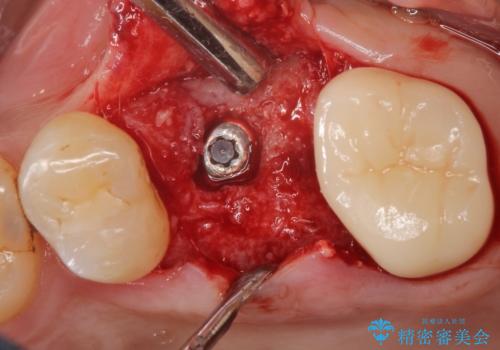

抜歯後、骨増生を行ったのちインプラントを埋入しています。